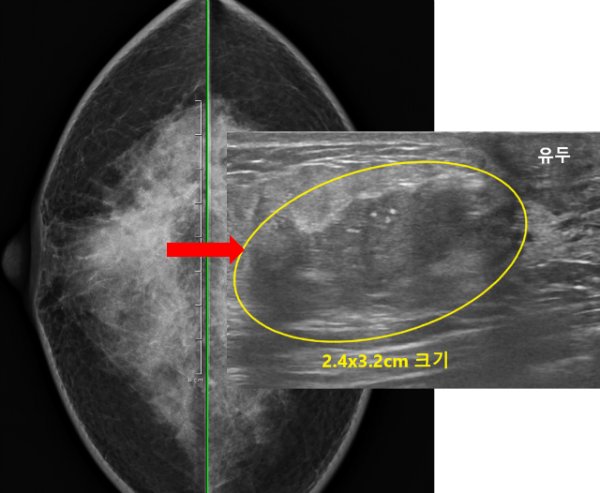

유방초음파 검사를 이어서 진행하였습니다.

유방초음파상 양쪽 유방에 작은 다발성 결절들이 관찰되었으며 그중 오른쪽 유방의 유두하부쪽에 약 2.4x3.2cm 크기의 불규칙한 모양과 경계를 보이는 결절이 관찰되었으며 이 결절이 진찰 및 유방촬영상 관찰된 병변이었습니다.